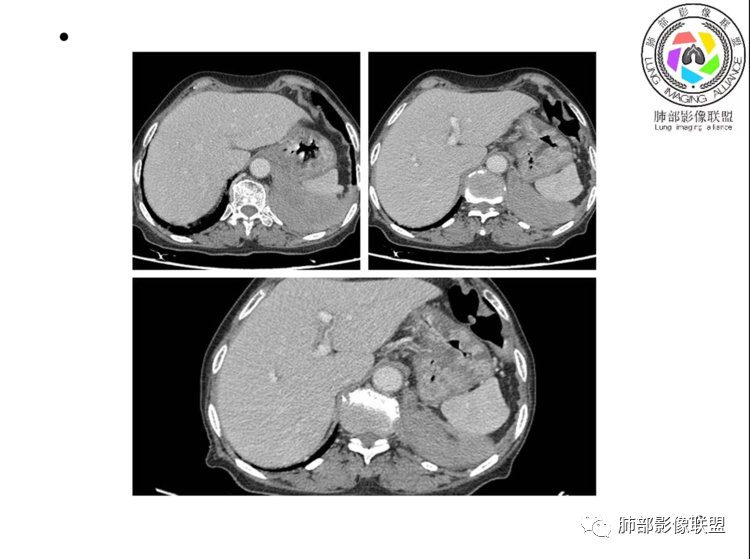

团片,内有支气管扩张,血管飘浮,不均匀强化,累膈肌似侵及脾脏,考虑恶性,淋巴瘤?肉瘤?

左肺下叶团块,边缘膨隆分叶,支气管部分阻塞、部分进入扩张,密度不均,延迟强化,血管走行正常,病灶与左侧膈肌分界不清。考虑恶性肿瘤:1淋巴瘤;2肉瘤样癌。

左肺下叶巨大实性肿块,支气管进入后阻塞,血管走行自然,增强中度均匀强化,无明显坏死。与膈肌分界不清,是否有侵犯导致腹痛症状?

考虑恶性肿瘤,低分化腺癌或者淋巴瘤?

老年女性,上腹部疼痛为主诉,CT所示左肺下叶肿块,左肺下叶支气管变窄,局部阻塞,病灶可见分叶,内见僵硬稍扩张的支气管,增强扫描病灶中度强化,内见血管造影征,首先考虑恶性病变,腺癌和淋巴瘤需要考虑,转移瘤待排除。

老年女性,以上腹痛就诊,左肺下叶团块影,边界清,可见分叶,延迟强化,内未见明显坏死,可见支气管充气扩张,血管走形自然,考虑淋巴瘤

老年女性,上腹痛就诊,CT可见左肺下叶巨大肿块,支气管进入后变窄堵塞,血管走行自然,内可见稍扩张支气管,增强均匀强化,与膈肌分界不清,考虑为恶性,淋巴瘤或腺癌可能

老年女性,左肺下叶软组织肿块,密度较均匀,边缘膨隆分叶,临近支气管截断,肿块内可见支气管穿行,与膈肌分界不清,增强后动脉期轻度均匀强化,静脉期呈渐进性强化,欠均匀,内血管走形如常,可见血管漂浮,整体感觉病灶偏软,考虑淋巴瘤可能大,鉴别腺癌。

患者老年女性,上腹部疼痛一周,无呼吸道症状,查体无阳性体征。血常规、尿常规、肝肾功能正常。肿瘤标志物CA125稍升高。胸部CT:左肺下叶肿块灶,边缘欠光滑,边界欠清楚,见分叶、血管集束征象,内见支气管扩张,增强中度强化,见血管漂浮征象。综合考虑恶性病变,淋巴瘤可能大,鉴别肺癌。

左下肺不规则巨大肿块,下叶支气管部分阻塞,部分扩张,与左侧膈肌分界不清,增强延迟强化,可见血管造影征,考虑恶性,淋巴瘤可能大,鉴别腺癌

老年女性,上腹部疼痛一周,肿标CA125升高。胸部CT:左肺下叶巨大肿块,分叶,密度不均,与左膈肌分界不清,内见枯枝征,部分支气管进入后截断,增强中度延迟强化,见血管漂浮征。胃壁不均匀增厚。考虑:恶性肿瘤病变伴阻塞性炎症,淋巴瘤?腺癌转移?鉴别TB、隔离等。

老年女性,左下肺大肿块、深分叶,考虑恶性肿瘤。纵隔肺门淋巴结无明显肿大,不支持小细胞癌;支气管进入后截断、肿块破坏力不强,不支持鳞癌,内部血管走行自然,不怎么支持腺癌,支持淋巴瘤;肉瘤似乎内部很少见支气管。

左肺下叶实变影,形态尚规则,外缘欠光滑,呈膨胀性生长,叶裂推移,近段支气管穿行,支气管略扩张,平扫密度均匀,增强后可见穿行血管,老年女性,无感染症状,实验室检查肿瘤标志物高,考虑恶性:1:淋巴瘤;2:腺癌;3:IMT

左下肺肿物,有分叶及血管飘浮征,定性恶性,无胸膜牵拉及毛刺,提示收缩力差,可排除腺癌。女性,肿块内坏死不明显(鳞烂心)不首选鳞癌。老年女性,血管飘浮,特别是膈肌受累首选淋巴瘤

定位,肺内,血管支气管穿行

定性,恶性,腺癌跟淋巴瘤鉴别

腺癌支持点就是常见病,发病率高,CEA高。不好解释血管穿行比较自然。病灶整体偏软,所以淋巴瘤放前面

考虑淋巴瘤!鉴别腺癌 首先看病灶恶性征象多,深分叶支气管截断,支气管感觉是受压闭塞,肺动脉显示良好,血管漂浮征!这么大肿瘤如果是鳞癌不可能没有坏死!腺鳞癌同样如此,肉瘤样癌同理,类癌、不典型类癌明显强化,而这例轻度延迟性比较均匀强化,淋巴瘤感觉是符合 特别是MALT

弥漫性大B细胞淋巴瘤